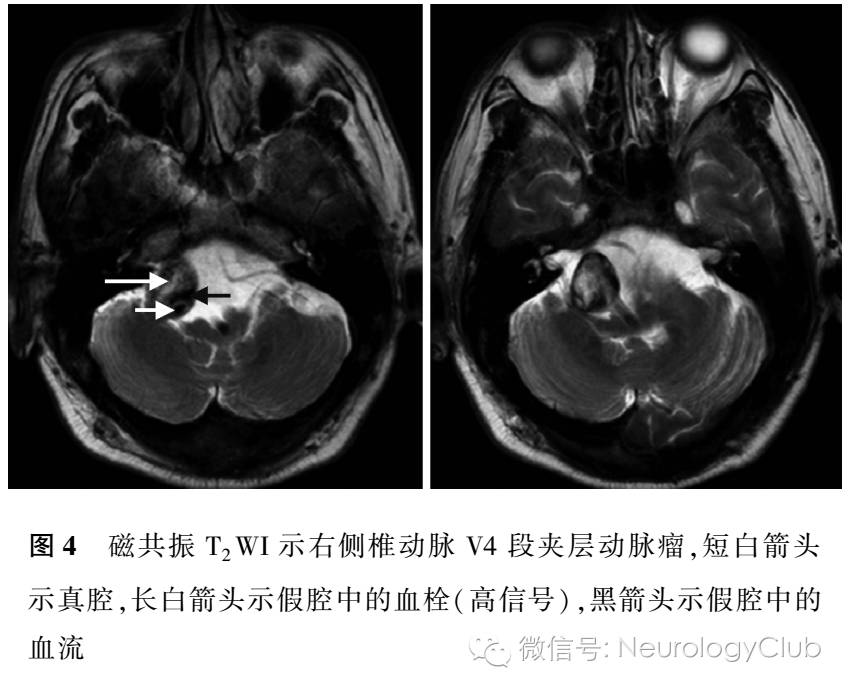

NCCT因其检查时间短、扫描速度快、不受金属器械及移植物影响等优势,可确定出血部位,估计出血量,判定出血是否破入脑室,并判断有无脑疝形成,是目前临床确诊急性脑出血的首选方法(图1),也是急诊鉴别缺血性卒中和出血性卒中、溶栓前排除脑出血最常规的筛查方法。NCCT可以显示直径>5mm呈高密度区的急性脑出血。急性期颅内出血,NCCT呈高密度,系血液中血红蛋白密度高于脑组织密度所致,多为圆形或卵圆形。约24h后,高密度血肿周围常有一低密度环存在,由于血肿周围的水肿和析出的血浆,通常在出血第5天最明显。随着时间的推移,NCCT上的特征性高密度影逐渐减弱、消失,大约在8-10d后变为低密度影,通常出血1个月时,整个血肿呈等密度或低密度。

MRI对于脑出血的诊断敏感度主要取决于出血时间及扫描序列,主要与血管内红细胞的完整性及血红蛋白的演变有关。MRI在脑出血急性期、亚急性期及恢复期T1WI和T2WI均有不同程度的表现,但是由于缺乏特征性的表现,不建议用于早期脑出血的诊断。梯度回波成像技术通过检测脱氧血红蛋白这一顺磁性物质在磁敏感序列梯度回波T2WI像上的显像,可以在急性期观察到低信号区内混杂斑块状信号,用于脑出血的早期诊断。近期研究发现MRI和CT对诊断急性脑出血的准确率均为96%,肯定了梯度回波序列对脑出血诊断的高敏感度和高特异度,与CT比较,还能检测到微出血病灶,获得更多的出血征象。